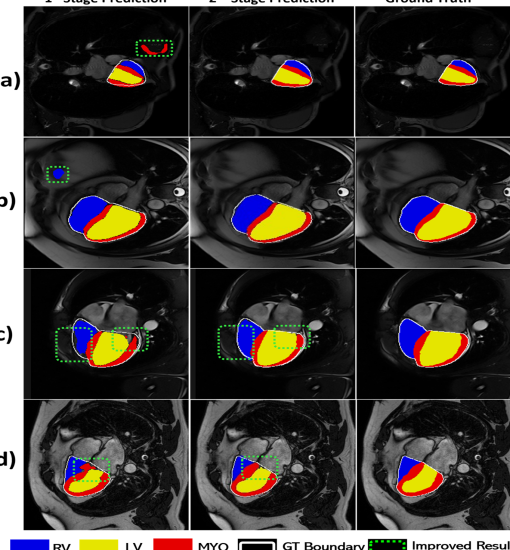

Fig. 3 depicts some problematic cases of stage-1 prediction.

The second stage of CroCNet serves as a refinement step, enhancing the segmentation fidelity from the first stage. The improvement in results is demonstrated in the last two rows in Table 1.

In another ablation study, we implemented the second-stage network without the specialist networks, presenting it as a single network without the inclusion of cross-E2A. The results are outlined in Table 2. While this strategy remains effective in refining the first stage predictions, there are instances where it might fail to precisely perform segmentation near the boundaries, illustrated in Fig. 4.

and hybrid utilizing both CNN and MHSA. Fig. 5 depicts the computational complexity of the proposed pipeline compared to existing methods. Results are provided from both stages, i.e. stage 1 (Proposed-s1) and 2 (CroCNet). Notably, the proposed method outperforms existing networks, even at stage 1. The stage 2 network contributes to further refinement, correcting erroneous predictions, as visually depicted in Fig. 3. In Fig. 3, the first column shows some erroneous segmentation examples of stage 1 networks. The middle column demonstrates the improvement achieved by the second stage in refining predictions from the first stage. The rightmost column provides the reference ground truth. Additionally, rows (a) and (b) depict how the cropping mechanism aids in removing outliers. Finally, observation from rows (c) and (d) shows that the cross E-2A among the encoder’s features of LV-Net, RV-Net, and MYO-Net contributes to further enhance the segmentation maps, particularly addressing disconnected edges in the areas of interest.